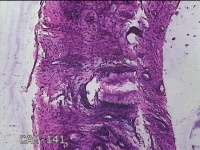

宫颈组织

性别

女

年龄

31岁

临床诊断

宫颈上皮内瘤变

一般病史

发现宫颈CIN2 2个月。

标本名称

大体所见

灰白暗红色组织2.8x1.8x0.3cm一块,表面糜烂,切面灰白暗红色,质软。

所提供图片不具有诊断价值。